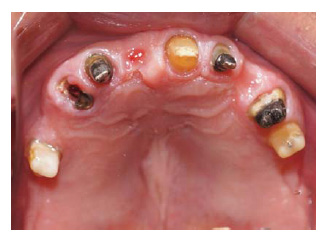

Se realizarón los exámenes clínicos, radiográficos y tomográficos necesarios llegando a los siguientes diagnósticos: Periodontitis crónica localizada moderada en las piezas 12,22,35 y severa en la pieza 15, deformidades y condiciones mucogingivales en rebordes edéntulos: Seibert III: Sextante IV y VI. Lesiones cariosas en piezas: 13,22,24,25, pérdida de sustancia dental causada por: Piezas talladas sin provisionales en piezas 34,35,44,15,12,21,22,24,25. Destrucción coronaria pieza 13, Diagnóstico pulpar: tratamiento de conductos previo piezas 15, 13, 12, 22, 24, Movilidad dental grado 3 en la pieza 15. Asimismo presentó un Desorden Funcional Oclusal teniendo como características: Edéntulo parcial: superior e inferior, Alteración de la guía anterior y disminución de dimensión vertical. (Figura 1 a y b).

Figura 1 a: Aspecto clínico del maxilar superior.

Figura 1 b: Aspecto clínico del maxilar inferior.